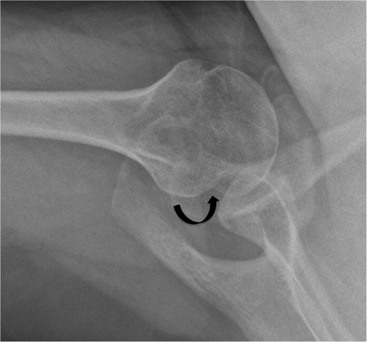

More severe injury may be associated with a bony injury of the glenoid rim, usually called a bony Bankart lesion (Fig. 46-10). Non-enhanced CT may occasionally be preferred to assess the size of the bony defect of the glenoid. There is usually associated impaction injury on the posterosuperior aspect of the humeral head called a Hill–Sachs defect (Figs. 46-11 and 46-12).

Two kinds of femoroacetabular impingement are described, cam type and pincer type, though these often coexist.20 Cam impingement is caused by the presence of an abnormal osseous ‘bump’ found on the anterior or lateral aspect of the femoral head–neck junction (Fig. 46-36). This produces abnormal contact between femur and acetabular rim in certain positions and typically presents in young athletic men. The α angle can be used to identify this loss of sphericity on a cross-table lateral radiograph or axial oblique MRI (Fig. 46-37). An α angle measuring greater than 50° may be taken as abnormal.21 Repeated contact between the osseous bump and the anterior acetabulum during hip flexion results in a labral tear and/or cartilage damage. CT is an excellent technique for demonstrating the bone morphology in this condition, although MR arthrography is able to show the cartilage and labral damage. Acetabular cartilage delamination (separation of the cartilage from the underlying bone), sometimes termed a ‘carpet lesion’, is common in cam-type impingement and may be detected on MR arthrography.22 The information provided by arthrographic MRI is important, as joint-sparing treatment (such as cam re-contouring) is unlikely to give effective symptom relief if there is established severe cartilage damage.